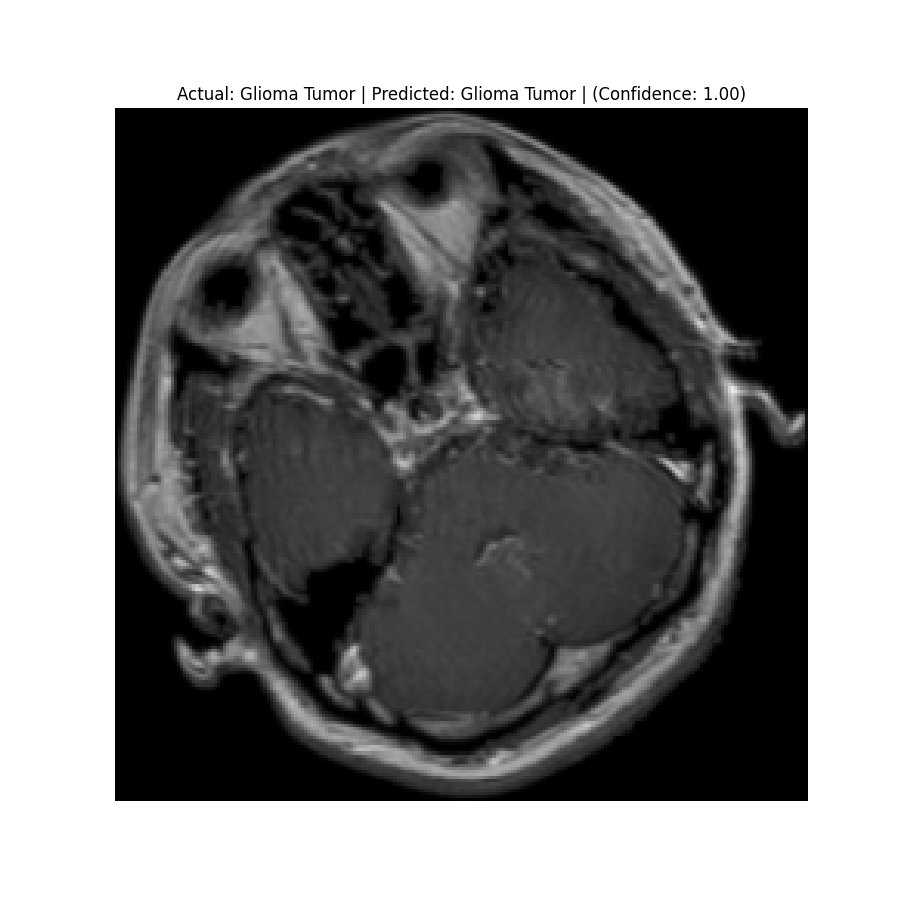

The dataset used in this project is the Brain Tumor Classification (MRI). It consists of MRI scans categorized into four classes: 👇

Glioma Tumor | Meningioma Tumor |

Normal | Pituitary Tumor |

Results

Check the predictions in the predictions folder. Below are some sample results:

![]() Actual: Glioma Tumor Predicted: Glioma Tumor (Confidence: 1.00) | ![]() Actual: Glioma Tumor Predicted: Glioma Tumor (Confidence: 1.00) |

![]() Actual: Meningioma Tumor Predicted: Meningioma Tumor (Confidence: 1.00) | ![]() Actual: Meningioma Tumor Predicted: Meningioma Tumor (Confidence: 0.81) |

![]() Actual: Normal Predicted: Normal (Confidence: 0.98) | ![]() Actual: Pituitary Tumor Predicted: Pituitary Tumor (Confidence: 0.99) |